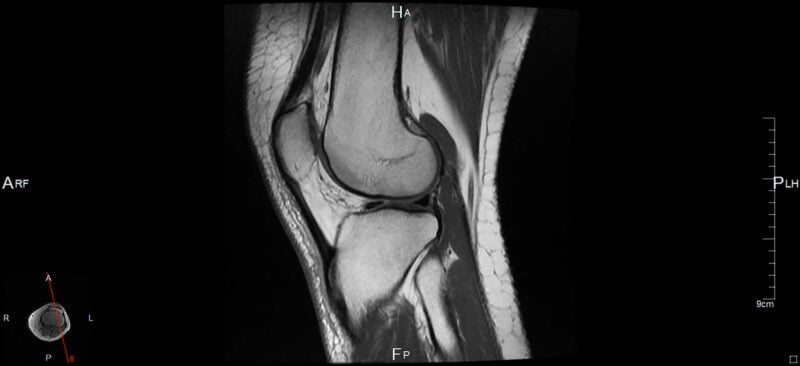

Come curare la cartilagine del ginocchio quando si consuma? A causa del dolore al ginocchio si può sospettare un problema o danno alla cartilagine. In questo caso per individuare l’eventuale danno è necessario fare degli esami diagnostici come la radiografia, la risonanza magnetica nucleare con oppure senza contrasto, la tomografia, la RMN oppure la TAC.